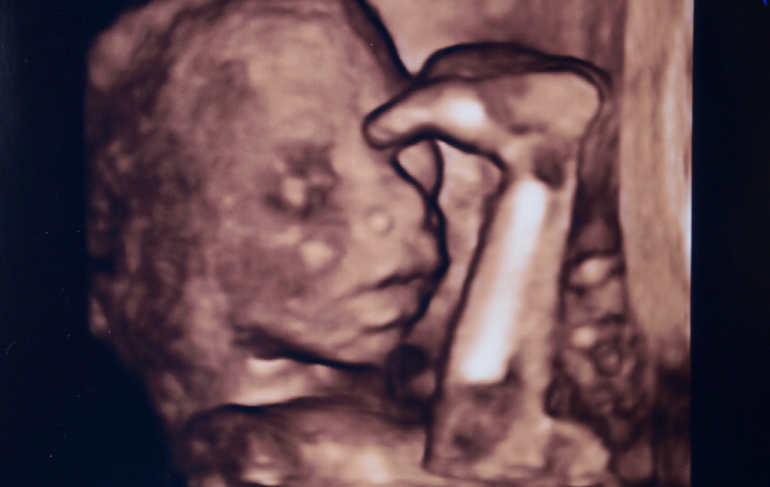

Прикладываю к посту фотографии малышки, сделанные в 20 и в 36 недель. Чтобы сразу становилось понятно, кто тут самый голодающий ;))

На консультации в ЖК, выбор женской консультации/гинекологаПосле "самовыписи" из Снегиревки, я полагала, что для того, чтобы от меня, наконец отстали, будет достаточно заключения заведующего кафедрой трансфузиологии Мечникова, что я гематологически здорова и результатов УЗИ, по которым прибавка моего несчастного, голодающего ребенка составляет 230 грамм в неделю. Что, кстати, даже больше среднестатистических норм. Для иллюстрации, на УЗИ 7 октября, в 33 недели дюймовочка весила 1500-1600 грамм. Через 9 дней, 16 октября, мы нахомячились до 1900-2000 грамм. Вчерашнее УЗИ, 28 октября показало как моя модель отъела изрядные щеки, а вес составил уже 2200-2300 грамм на сроке 36 недель. Кстати, прибавка веса была одинаковой как в условиях больницы, так и на вольных хлебах. Поэтому есть повод задуматься о том, что развитие малышки идет своим чередом, несмотря на пляски теть с иголками и переживания маман)